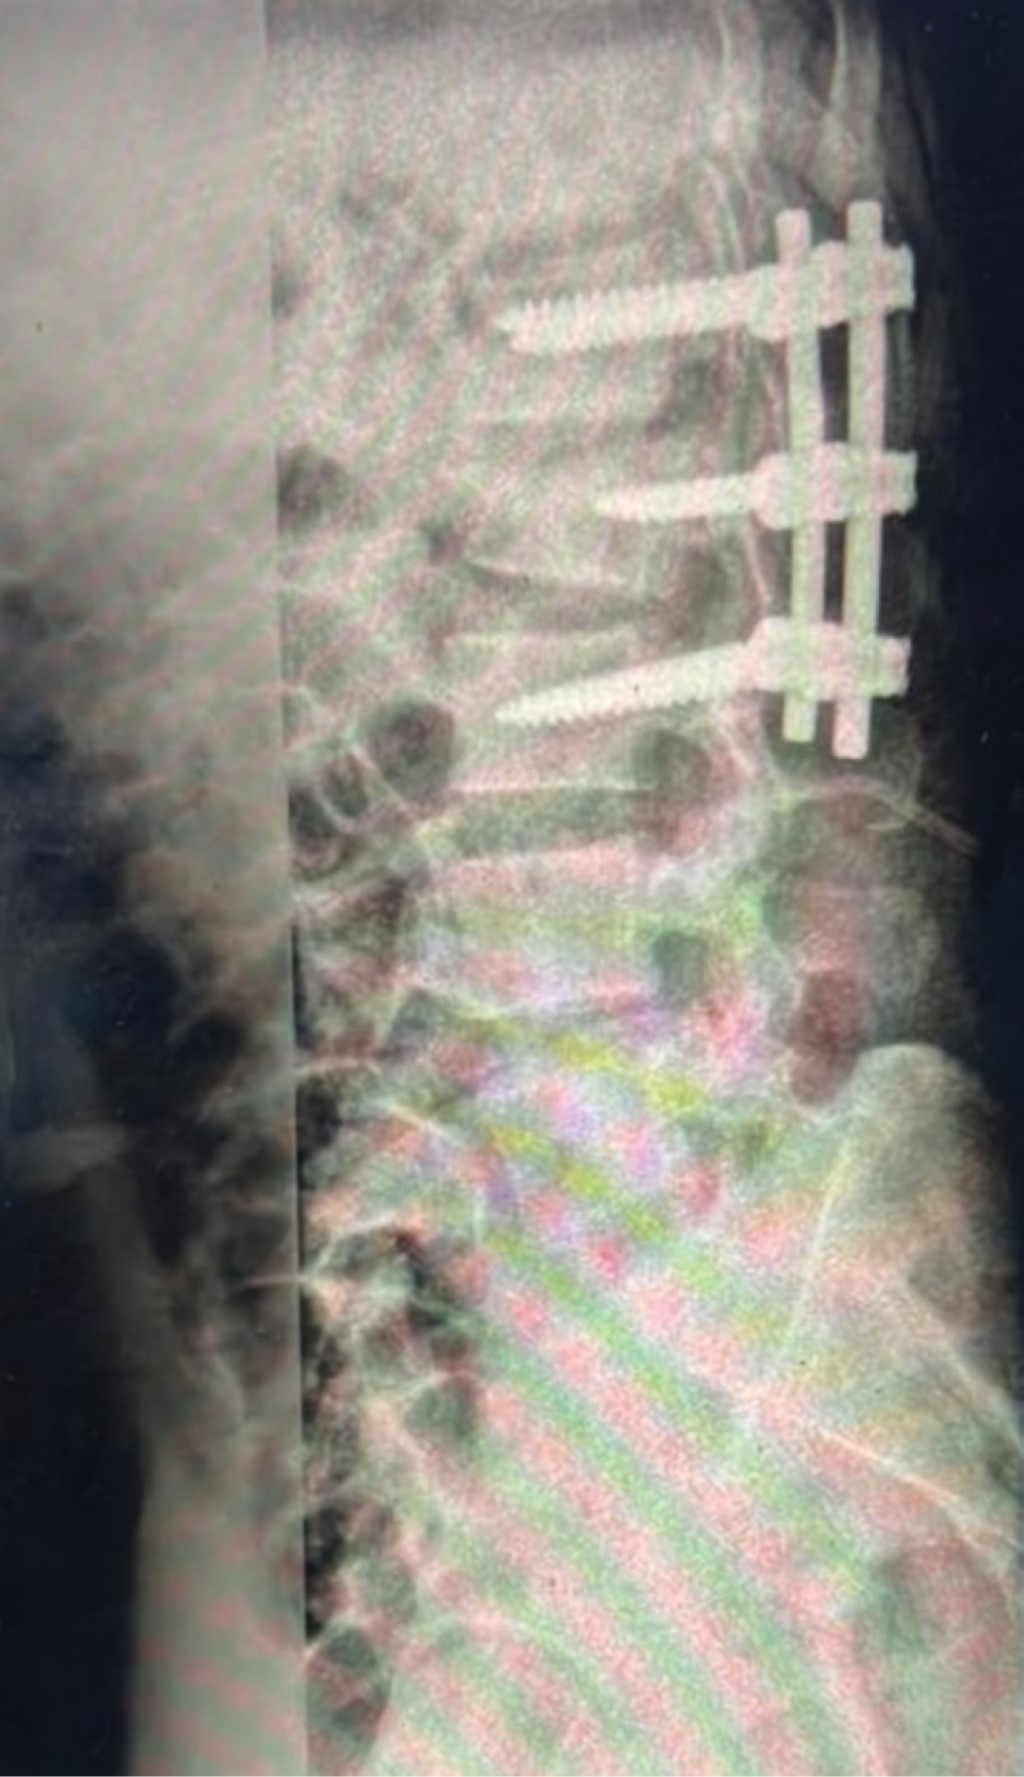

Figure 2